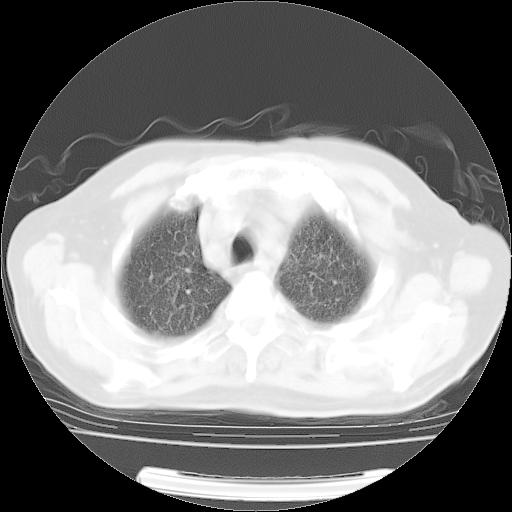

4月14日肺部CT

肺部CT平扫未见异常。